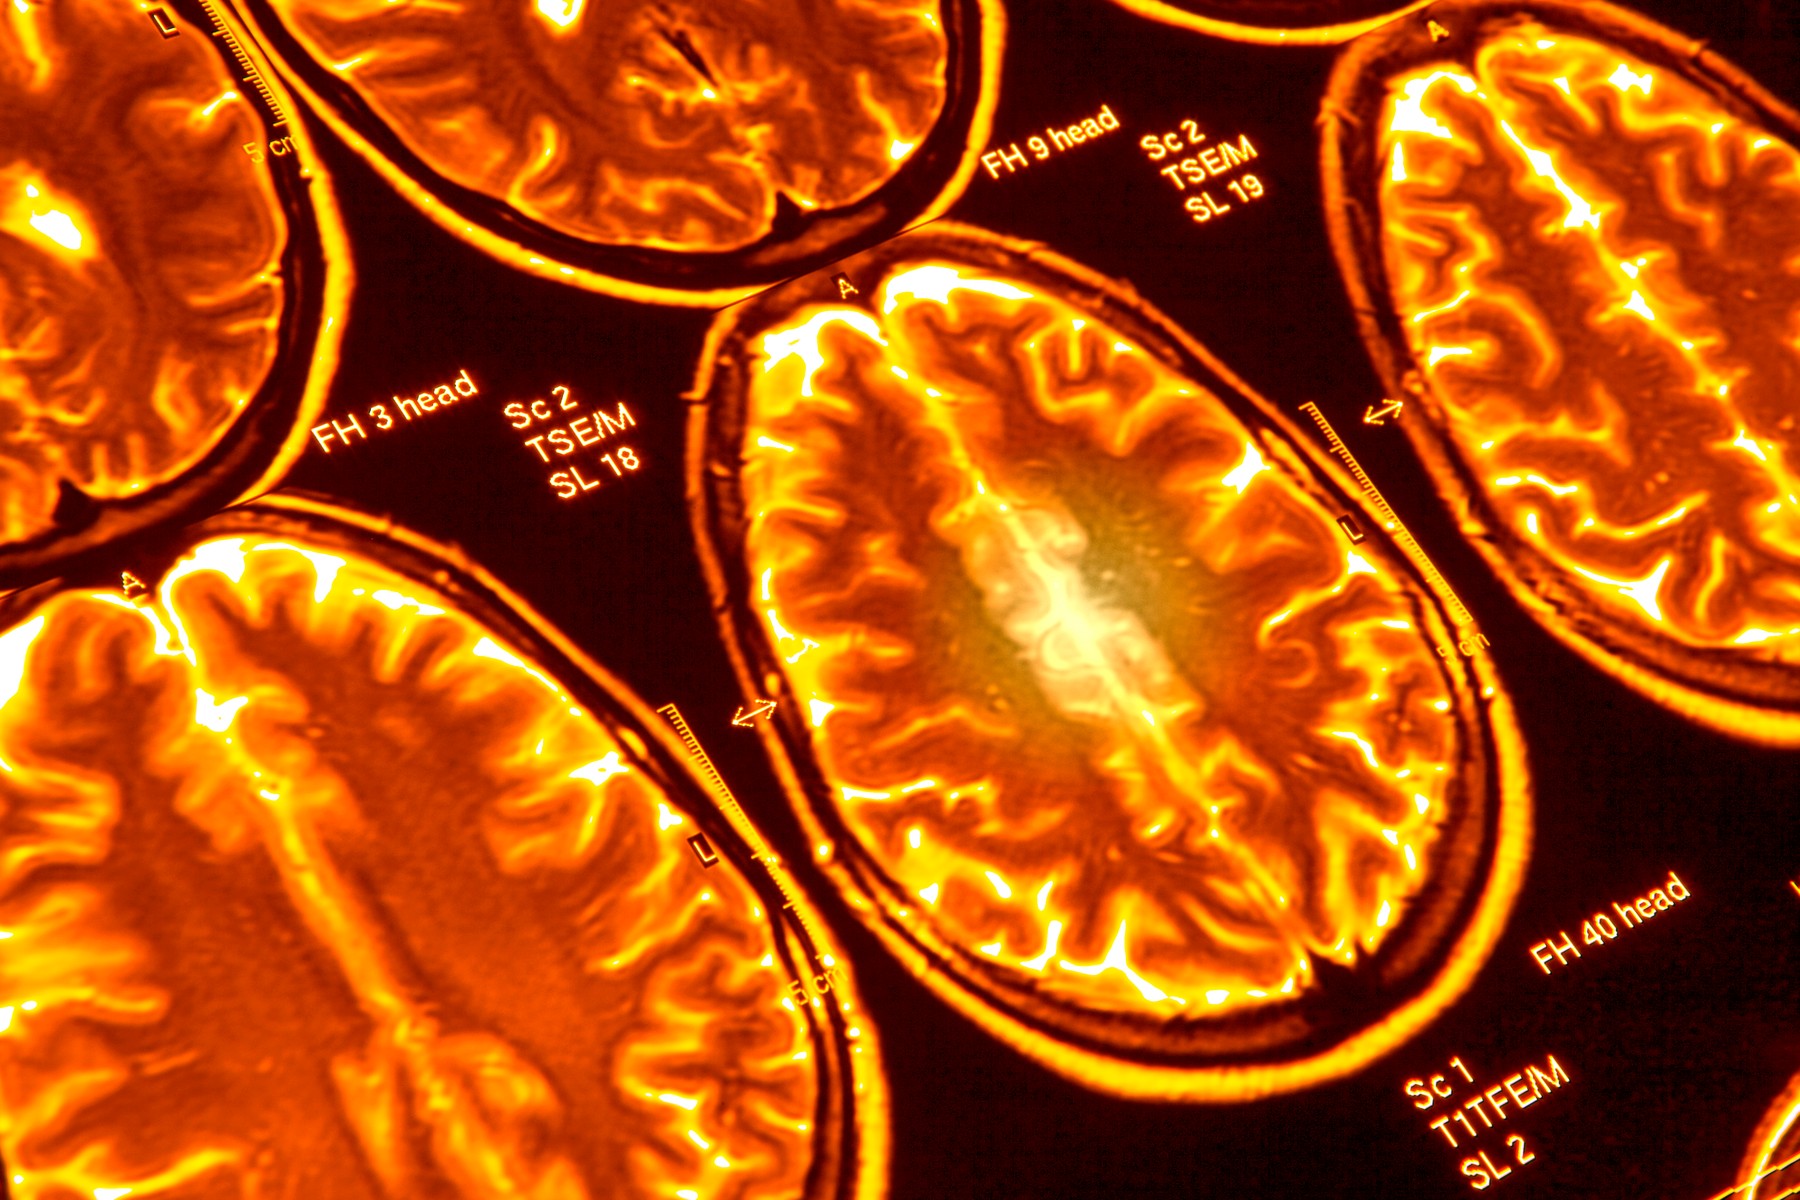

Foto: Science Photo Library / Sciencephoto / Profimedia Foto: Science Photo Library / Sciencephoto / Profimedia Foto: Science Photo Library / Sciencephoto / Profimedia Korona trajno oštećuje mozak i osobama sa blažim simptomima autor: Božica Luković Zdravlje 09. jul. 2020. 12:13 0 Podeli vest: Pojavilo se upozorenje da koronavirus ostavlja užasne posledice na mozgu, i to kod osoba koje imaju blaže simptome infekcije. Podeli vest: Oglas Juče je objavljena neurološka studija koja je sprovedena nad više od 40 pacijenata zaraženih koronavirusom u Velikoj Britaniji. Ti pacijenti su imali komplikacije koje su se kretale od upale mozga i delirijuma do oštećenja živaca i moždanog udara.U nekim slučajevima neurološki problem bio je prvi i glavni simptom kod pacijenta, prenosi Index.Britanski stručnjaci su u toku prvog talasa koronavirusa primetili porast opasnog stanja kod pacijenata koje se zove akutni diseminirani encefalomijelitis (ADEM). To je retka upalna demijelinizirajuća bolest živčanog sistema.Na UCL-ovom Institutu za neurologiju, primećeno je kako su se slučajevi ADEM-a povećali s jednog mesečno pre pandemije na dva ili tri nedeljno u aprilu i maju. Jedna 59-godišnja žena umrla je od komplikacija, piše Gardijan.Desetak pacijenata imalo je upalu središnjeg živčanog sistema, 10 je imalo bolest mozga s delirijumom ili psihozom, osam je imalo moždane udare, a dodatnih osam je imalo lošu funkciju perifernih živaca, najčešće dijagnostikovanu kao Gulen-Bareov sindrom, odnosno imunološku reakciju koja napada živce i uzrokuje paralizu, a koja je fatalna u 5% slučajeva."Primetili smo da covid-19 utiče na mozak različito od drugih virusa", rekao je neurolog Majkl Zandi, jedan od autora istraživanja.Ovi slučajevi su podigli veći svest o zabrinjavajućim dugoročnim posledicama koronavirusa na organizam. Neki pacijenti su nakon oporavka ostajali bez daha, a drugi su imali problema s ukočenošću, slabošću i pamćenjem.Jedna pacijentkinja (55) koja se zarazila koronom, a nije imala istoriju psihičkih bolesti, čiji je slučaj su opisali u studiji, počela je da se čudno ponaša dan nakon što je otpuštena iz bolnice. Više puta je obukla kaput i opet ga skinula. Počela je i da halucinira, rekavši da je u svojoj kući videla majmune. Primljena je u bolnicu i postepeno joj je bilo bolje tek nakon terapije antipsihoticima.Još jedan slučaj je jako čudan - pacijentkinja (47) primljena je u bolnicu s glavoboljom i ukočenošću u desnoj ruci sedam dana nakon pojave simptoma korone - kašlja i visoke temperature. Ubrzo je prestala da komunicira sa okolinom pa su operacijom morali da joj uklone deo lobanje kako bi se ublažio pritisak na natečeni mozak."Želimo da medicinari širom sveta budu upoznati sa svim komplikacijama koronavirusa", kazao je Zandi i pozvao lekare i sve druge zdravstvene radnike da se savjetuju s neurolozima ako kod zaraženih primete simptome kao što su problemi s pamćenjem, umor, ukočenost ili slabost.Još jedna loša pojava na koju ukazuju naučnici je da bi virus mogao da kod manjine populacije ostavi suptilna oštećenja mozga koja se primećuju tek u nadolazećim godinama. Primer iz istorije takođe upozorava: tokom pandemije gripa 1918. godine, skoro milion ljudi je kasnije dobilo neko psihičko oboljenje.Čitavo istaživanje, objavljeno u naučnom časopisu "Brain" možete pročitati ovde.***Pratite nas i na društvenim mrežama:FacebookTwitterInstagram Kako da se zaštitiš od virusa koji lebdi u vazduhu Zdravlje 0 Upozorenje stručnjaka: Suzavac olakšava širenje koronavirusa Zdravlje 0 SZO priznala: Postoje novi dokazi, pogrešili smo sa koronom Zdravlje 0 koronavirus mozak oštećenje psihički problemi zdravlje Pratite nas na društvenim mrežama: Koje je tvoje mišljenje o ovoj temi? Učestvuj u diskusiji ili pročitaj komentare Budite prvi koji će ostaviti komentar Pošalji komentar Pročitaj komentare (0)